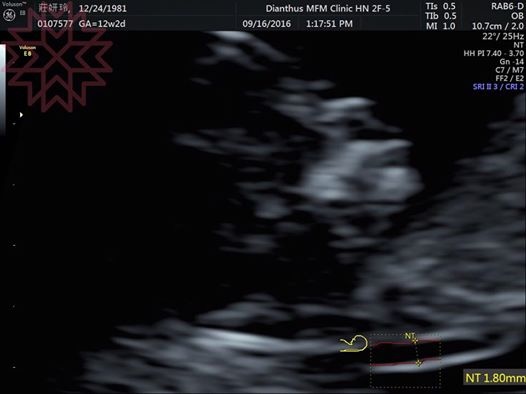

10W抽完血以後要等到12W才能做初唐超音波

檢查頸部透明帶和其他軟指標(鼻樑骨、三尖瓣、靜脈導管有無逆流)

幸好這孩子很識相,等醫生來檢查的時候終於躺到正確位置

(紅色虛線的地方就是頸部透明帶)